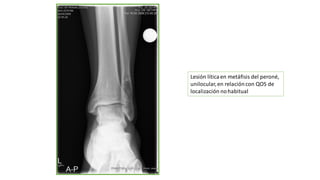

Lesión líticaen metáfisis del peroné,

unilocular,en relacióncon QOS de

localización nohabitual